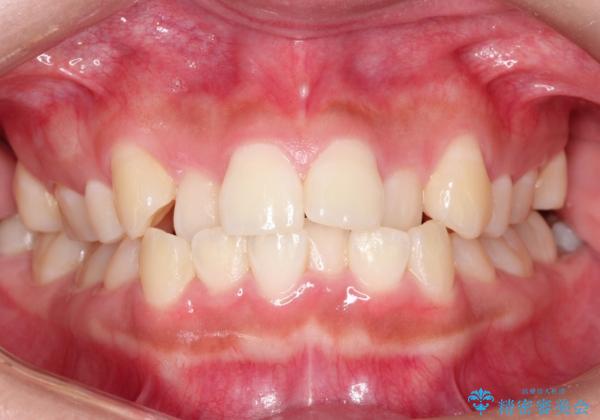

- 前歯のでこぼこが気になると来院されました。

奥歯の噛み合わせは綺麗に噛んでいたため、前歯の叢生(でこぼこ)を、短期間で治療完了するように計画しました。

前歯のガタツキを改善する治療法として、マウスピース矯正が適していることが多いです。

マウスピース矯正は、金属製のブラケットやワイヤーを使用せずに、透明なマウスピースを装着して歯を移動させる方法です。そのため、目立たず、痛みも少ないです。